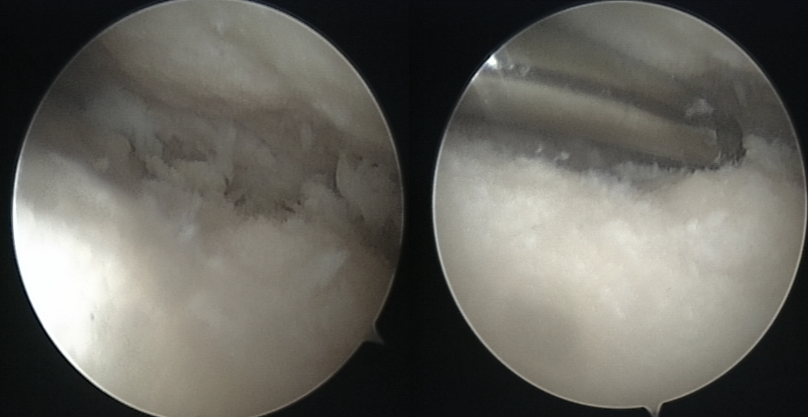

软骨退变

游离体形成

关节清理术后

清除的骨赘及游离体

剥脱性骨软骨炎

王会余 男  65岁

软骨剥脱